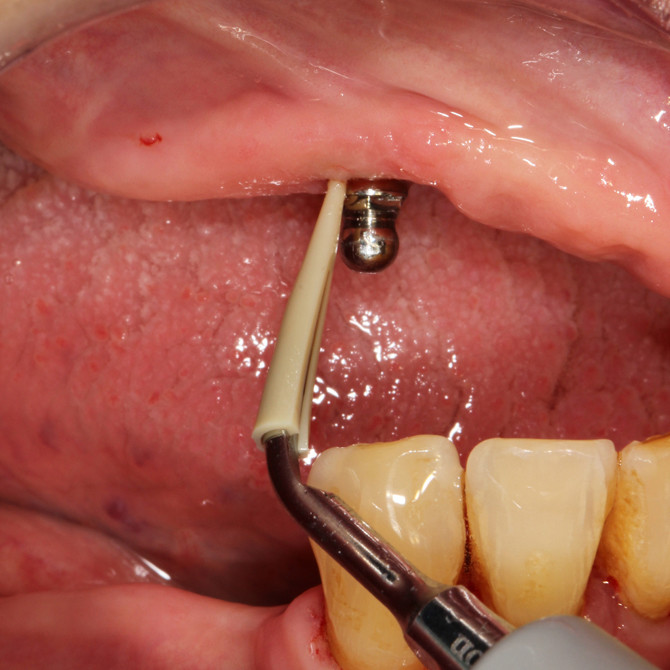

Metallfreier Spezial Aufsatz aus hochwertigem Kunststoff (PEEK) entfernt mühelos Plaque und Zahnstein von Implantatoberflächen und Restaurationen aus Metall oder Keramik

Keine Beschädigung oder Abrasion von Titanoberflächen

Reinigung unter Spülung und Speichelabsaugung

Ultraschallaufsatz OHNE Spezial Kunststoffspitze – zur supragingivalen Entfernung von Konkrementen MIT Spezial Kunststoffspitze – für die schonende Implantatprophylaxe